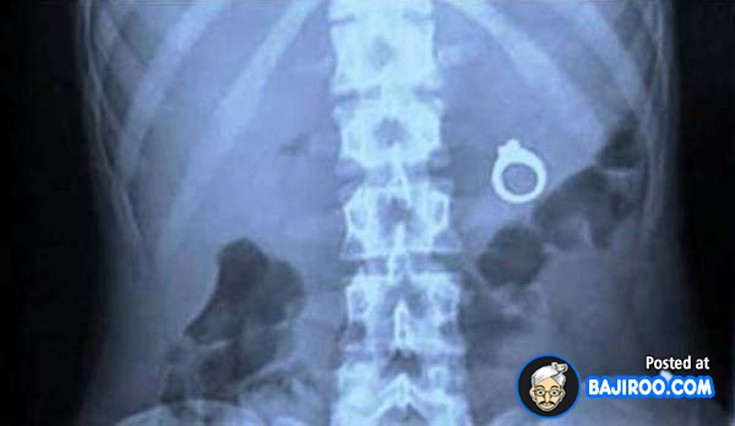

Ο,ΤΙ ΝΑ 'ΝΑΙ #ακτινογραφίες Παράξενα πράγματα που έχουν δείξει οι ακτινογραφίες Από δαχτυλίδια μέχρι πιρούνια και καρφιά - Δείτε τις φωτογραφίες 15·04·2016 11:08 1 σχόλια